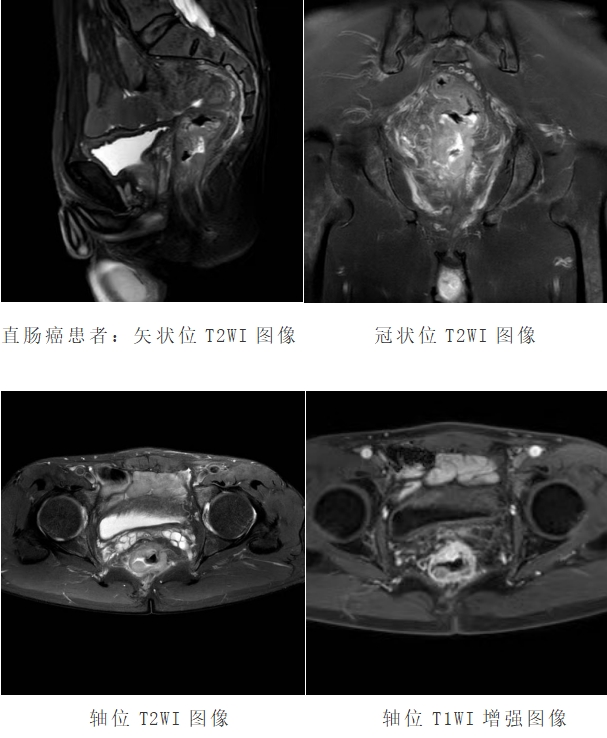

直肠磁共振具有较高的软组织分辨率、无辐射和多方位成像的优点,可清楚显示肿瘤与周围结构的关系。在 T2WI 图像上,可清晰显示直肠壁的三层结构,对于直肠癌的临床分期具有重要作用,从而为患者个体化的治疗和预后评估提供有力支持。